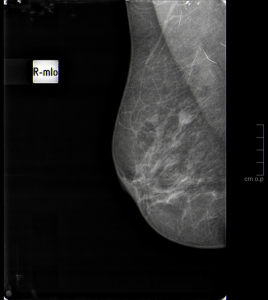

La prueba de elección es la mamografía debido a su alta sensibilidad y especificidad para detectar el cáncer de mama incluso en los estadios más precoces. Además es una técnica de bajo coste, gran disponibilidad, fácil acceso a la población, no es invasiva y no causa daño, ya que la cantidad de radiación recibida es mínima. Todas estas características la convierten en el gold estándar para esta patología.

Se utiliza tanto para la detección del cáncer temprano de mama como para el estudio de pacientes en las que se observan alteraciones clínicas, como es este caso.

A pesar de ello, la mamografía tiene algunas limitaciones, especialmente en las mujeres jóvenes, debido a que sus mamas suelen tener un tejido glandular denso. En ese caso, se complementa con una ecografía.